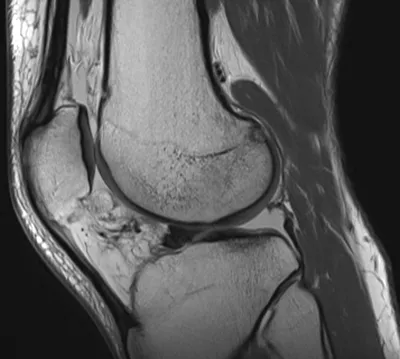

Posterior meniscocapsular ligament injury

MRIKneeSagittal+2